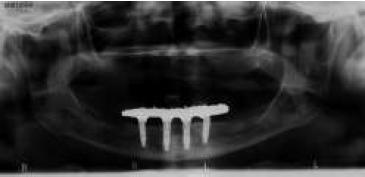

La planificación se realizó por medio de una ortopantomografía (fig. 5), evitando la utilización de cone-beam, siguiendo nuestro objetivo de realizar un tratamiento con un bajo costo. Al momento de la cirugía la paciente se encontraba premedicada con amoxicilina de 500 mg cada 8 h desde el día anterior15,16, ibuprofeno 400 mg cada 8 h10, comenzando 1 h antes de la cirugía17 y colutorios de clorhexidina al 0,12%, habiendo iniciado el tratamiento 48 h antes del procedimiento quirúrgico4. En el pabellón se probó nuevamente la guía multifuncional en boca (fig. 6), se anestesió a la paciente para luego realizar una incisión crestal desde la zona del primer molar derecho a la zona del primer molar izquierdo10,15,18, con incisiones liberadoras bilaterales, para luego realizar la disección subperióstica lingual y vestibular18. Con la plantilla radiográfica proporcionada por el fabricante se seleccionó sobre la radiografía panorámica el largo de los implantes a colocar. La cantidad de tejido óseo en sentido vestíbulo-lingual observada durante la cirugía fue de 5-6 mm, por lo que los implantes utilizados fueron implantes cónicos Strong SW de hexágono interno (SIN®, Sao Paulo, Brasil) de 3,8 mm de diámetro. Con la ayuda de la guía como referencia, se colocó 2 implantes distales, uno en cada lado, en la zona de los primeros premolares, inclinados a distal5, teniendo una longitud de 13 mm. Otros 2 implantes se colocaron a cada lado de la línea media mandibular, con una longitud de 15 mm. Se comprobó que los 4 implantes tuviesen una estabilidad primaria superior a los 30 N/cm (fig. 7). Se instalaron pilares Mini-Abutment y cilindros de protección de pilar, también teniendo como referencia la guía multifuncional. Se eligió suturar los tejidos con sutura no reabsorbible 4-018,19 (Seda, Ethicon, Johnson & Johnson, Brasil), siguiendo nuestro objetivo de disminuir los costos del procedimiento, y se envió a la paciente a la sala de recuperación (fig. 8).